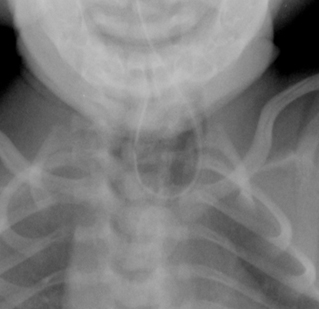

Fístula traqueoesofágica: sonda orogástrica torcida no esôfago

Do acervo de Ponthenkandath Sasidharan, MD; usado com permissão